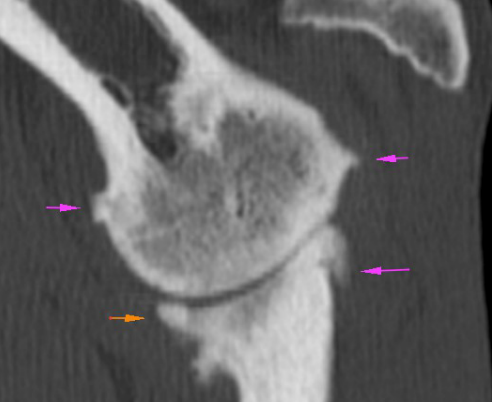

We had a CT scan done. It was expensive but I reckoned at least I would have a better idea of what the problem was.

Aside from the limp Archie seems pretty upbeat and active but the CT report listed a whole bunch of things. There was problems in his elbows, as suspected (bilateral medial coronoid disease and elbow osteoarthrosis), his back (more long names), his small intestine (a metallic object possibly in the intestinal lining – really? What IS that?) and an enlarged prostate. They do say ‘if you don’t want the answer, don’t ask the question’. On the plus side you could say I got my money’s worth. At least I have some pretty cool images to share, here’s some of them.